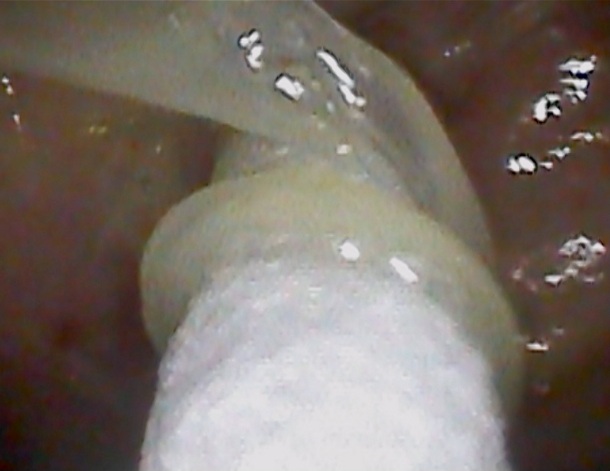

これは 「3日前から耳が痛くて聞こえが悪い」とのことで当院受診された患者の耳

の写真です。

外耳道に、膿&カビの塊が充満しています。

原因は耳掃除のし過ぎで耳の穴を傷つけ、そこにカビが付着し増殖という患者さんが多いです。傷がついた後で 長時間イヤホンを付けて生活している場合はハイリスクとなります。

治療としては、まずは耳鼻科を受診し耳の中を綺麗にすることです。抗真菌薬投与、さらに耳を触らないことが大切です。

実は、今回受診された患者さん 7年前にも外耳道真菌の診断での治療歴がございます↓

カビは治療でいったん消えたあとでも、繰り返しやすいという特徴があります。

耳

は診てみないと分かりません。耳症状のある方は、耳鼻咽喉科の受診をおススメいたします